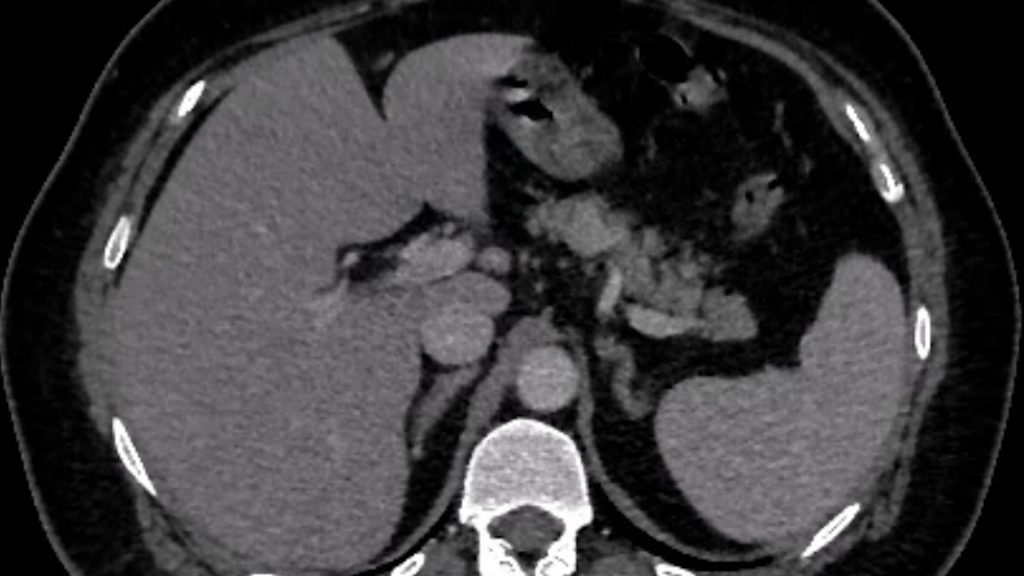

Cazul lunii

Over-the-scope-clip duodenal

Bărbat in vârstă de 70 de ani, internat pentru vărsături și diaree, simptome debutate cu 24h anterior prezentării. Fără dureri abdominale, fără febra sau frisoane. Istoricul medical descrie fibrilație atrială si mutație a protrombinei cu multiple episoade de embolie pulmonara (tratament cu Acenocumarol la domiciliu); insuficienta cardiaca cronica; hipertensiune arteriala; hipertensiune pulmonara; proteza de genunchi drept cu multiple intervenții chirurgicale, inclusiv episod de sepsis – tratament cronic antibiotic la domiciliu (Amoxicilină + Tetraciclină); tulburare neurocognitivă.